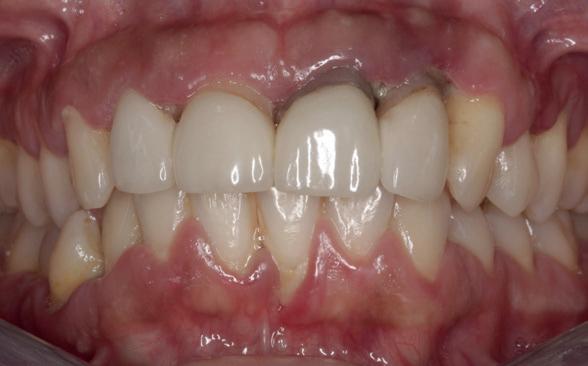

De diagnose luidde lokaal parodontitis met ernstige furcatie aandoeningen; Stadium IV (vergevorderd); graad C (snel progressief) (afbeelding 7) De elementen die niet te behouden waren, werden geëxtraheerd.

Tijdelijke voorzieningen werden getroffen in de vorm van een etsbrug in de bovenkaak en een uitneembare voorziening voor de onderkaak.

Na afronding van de eerste twee behandelstappen werd parodontale stabiliteit bereikt, zoals waarneembaar op de parodontiumstatus en (röntgen)foto’s (afbeelding 6, 8). De patiënt toonde aantoonbare verbetering in mondhygiëne (afbeelding 4) en bleef gemotiveerd om de behandeling voort te zetten.